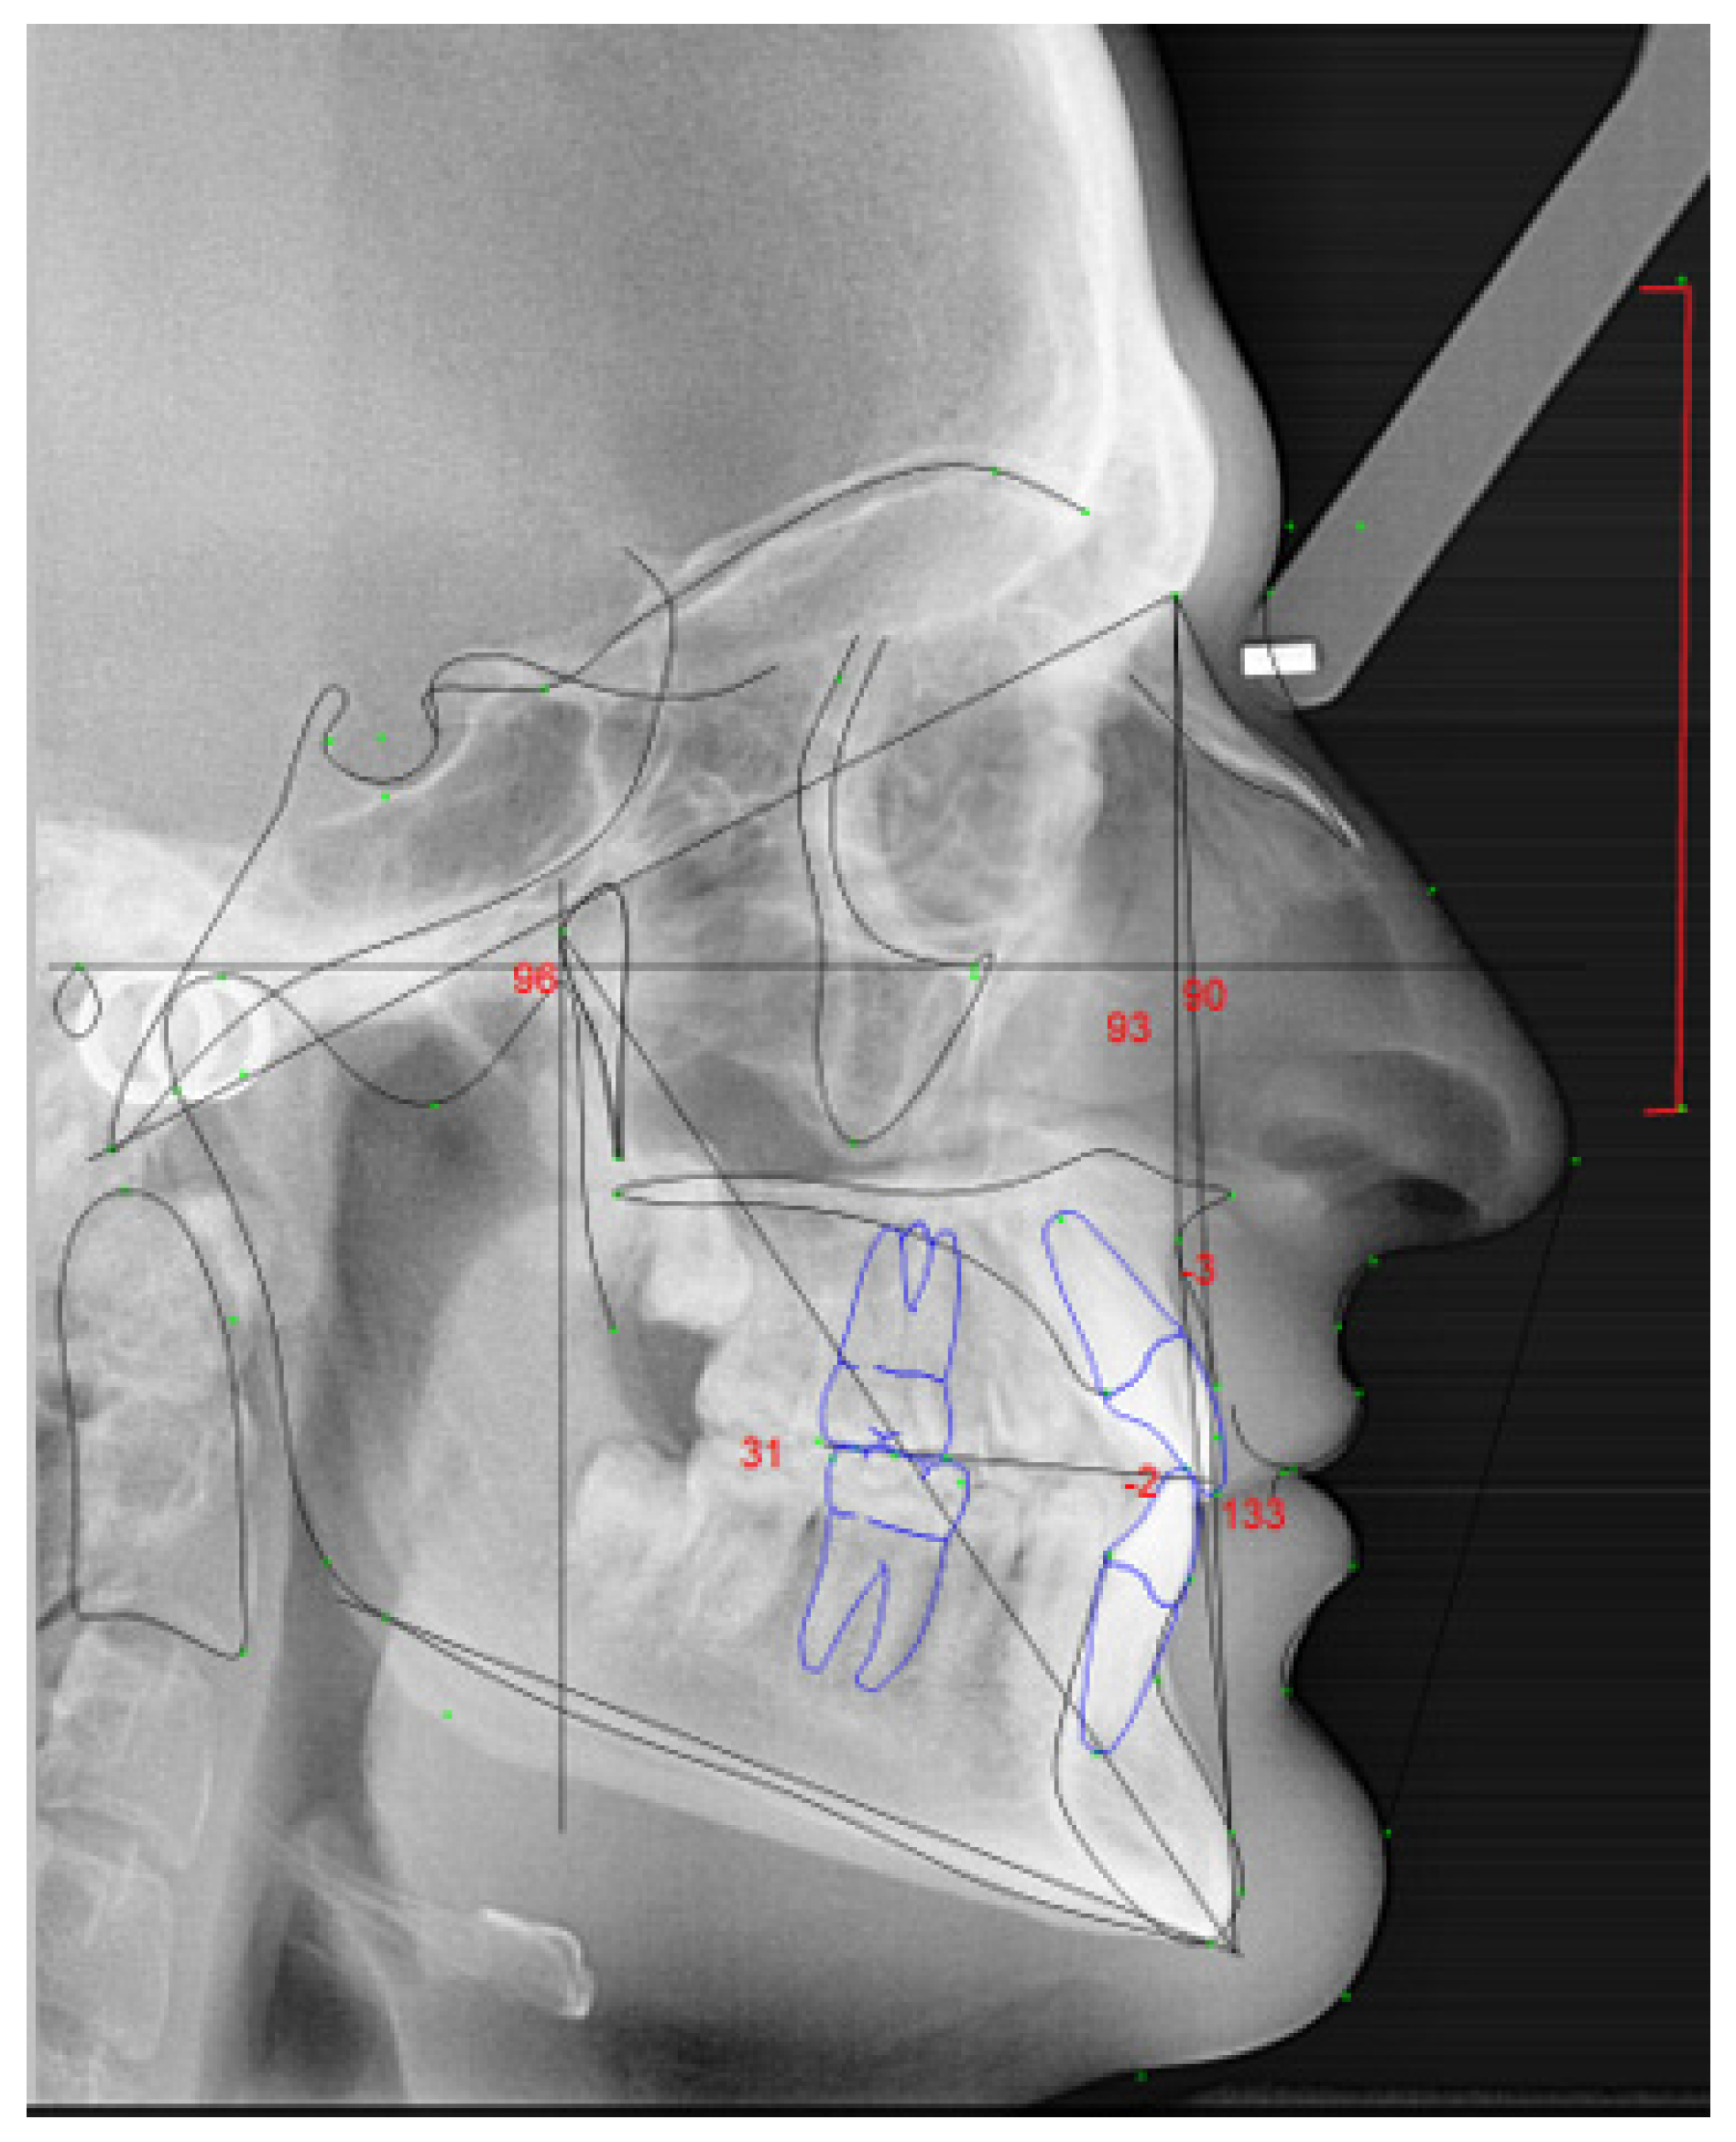

To collect the lateral cephalograms (Figure 1) Orthoralix 9200- Gendex, KaVo, Biberach an der RiB, Germany, from the Faculdade de Medicina Dentária da Universidade do Porto was used. The images were taken to both string and wind instrumentalists, in maximum intercuspidation by the same technician to allow a standardization of the protocol. The participants were told to not move during the imaging acquisition, look forward, feet aligned, head in rest position, but in the orthostatic position. The participants were told to hold their head in a stabilized position with the olives in external auditory meatus, and with the indicator supporting the glabella. The subject’s sagittal plane was perpendicular to the path of the X-ray. The Frankfurt (horizontal) plane was parallel to the floor. To all participants was given a lead vest to minimize the radiation exposure.

• Overjet: anterior-posterior overlap of the upper incisors over the lower incisors (in white, Figure 3a);

• Overbite: superior–inferior overlap of the upper incisors over the lower incisors measured relative to the incisal ridges (in blue, Figure 3a);

• Lower incisor protrusion: distance between the coronary extremity of the lower incisor to the A/Pog line (in red, Figure 3b).